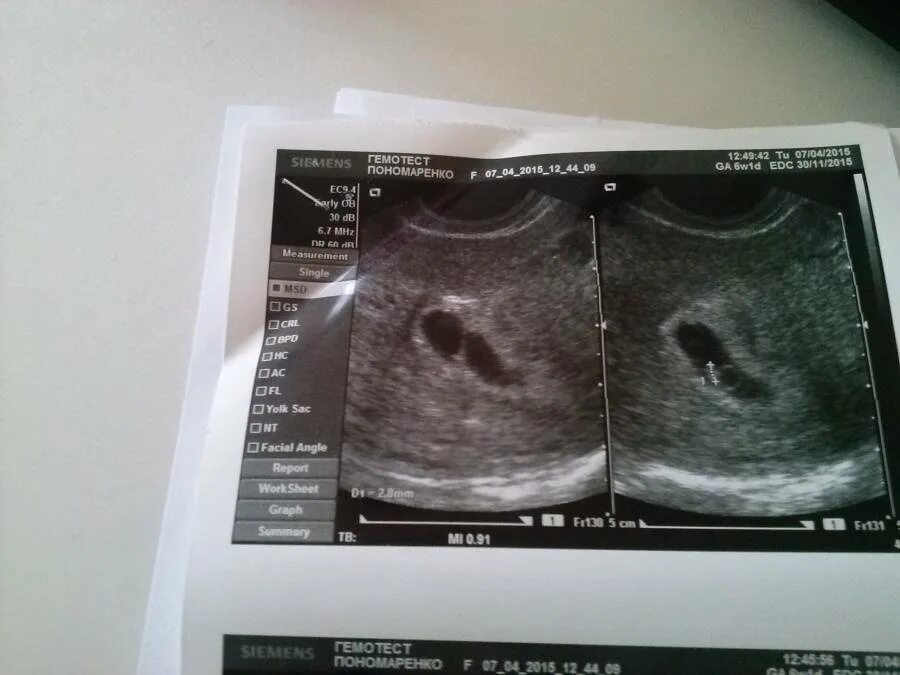

Беременность 6 недель после